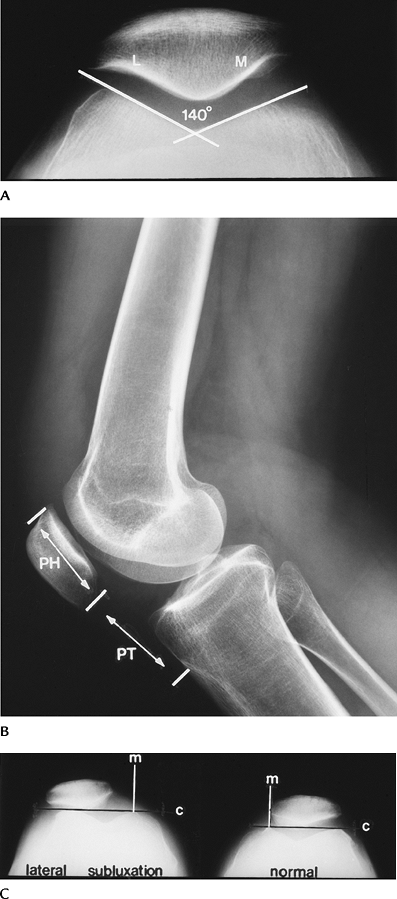

![]() |

FIGURE 5-31 (A) Normal PCL with an angle (lines) of 140 degrees. Normal greater than 113 to 114 degrees. (B) ACL tear with hooked PCL (broken line). (C) ACL tear with hooked PCL and angle (lines) of less than 90 degrees.